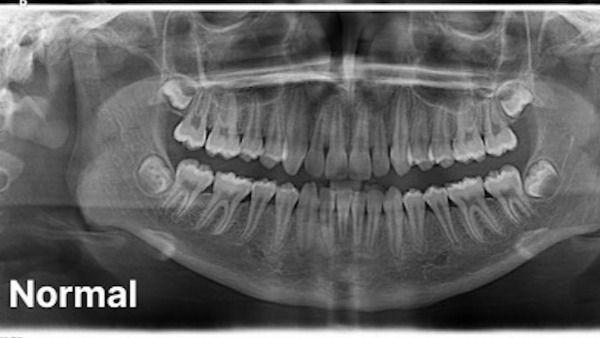

Le jeune homme de 26 ans est atteint d’une forme d’hypodontie génétique. Il lui manque ainsi cinq dents d’adultes et toute ses dents de sagesse. Ses cinq dents de lait qui auraient dû tomber naturellement sont restées en place trop longtemps, aucune dent ne se trouvant dessous pour les faire tomber. Elle ont ainsi commencé à pourrir à l’intérieur de sa bouche.

Ses autres dents se détériorent égaement rapidement. Tristen, qui perd des bouts de dents chaque mois, raconte que frotter sa langue contre ses dents est «comme la frotter sur du verre brisé». Il ne lui reste plus que cinq ou six dents du haut intactes.

Une dentition normale comparée à celle de Tristen